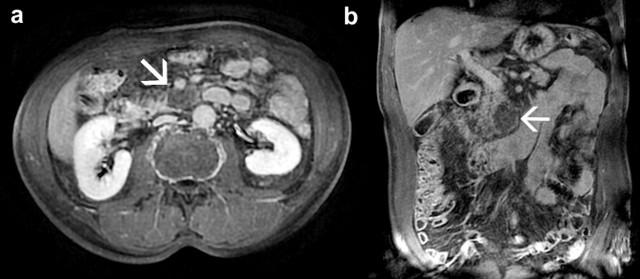

Workup firstly comprised laboratory analyses (including serum CEA, CA 19-9, alphafetoprotein and chromogranin-A) that were found normal and abdominal CT that showed the presence of a hypodense homogeneous lesion in the uncinate process of the pancreas. The lesion was well-defined, with oval shape and dimensions of 32x19x36 mm (Figure 1). We decided to continue the investigations with abdominal MRI that confirmed the presence of the pancreatic lesion appearing with clear-cut margins, moderately T2 hyperintense and without enhancement after paramagnetic contrast agent (Figure 2).

Figure 2. Axial (a.) and coronal (b.) magnetic resonance imaging scans of the abdomen showing the presence of a clear-cut margins lesion in the pancreatic head (white arrows). |